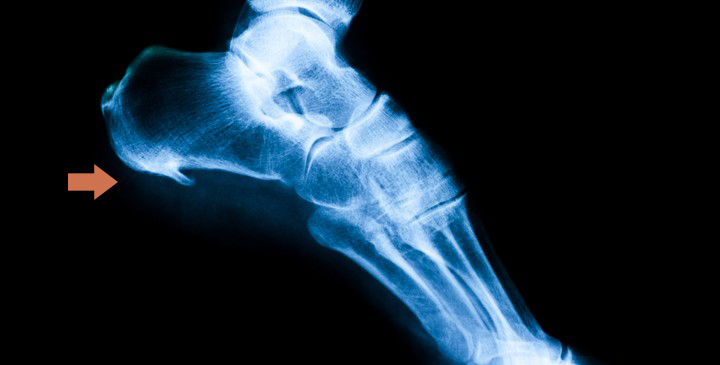

El espolón calcáneo es un crecimiento del hueso del talón en forma triangular o de lanza. Se produce cuando la fascia plantar (tejido elástico que une el talón con la zona de debajo de los dedos del pie) está sometida a excesiva tracción y sobrecarga generando unas microrroturas en su inserción. Esta parte se calcifica formándose esa especie de “hueso” que provoca un dolor agudo en el talón, como si fuesen pinchazos.

Tras ello, se procede al examen clínico, que suele ser suficiente para detectar esta patología. Lo aconsejable es realizar una prueba radiológica en la que se observará si existe esa calcificación que tendrá forma de “saliente puntiagudo” que sale desde el talón hacia el interior del pie. Si en esta prueba no aparece esta nueva formación, hablaremos de fascitis plantar. Se puede decir, aunque con algunos matices, que el espolón es la continuación natural de una fascitis mantenida en el tiempo.